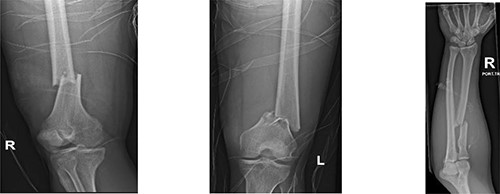

Resuscitation was carried on with 2 l of normal saline and two PRBC units to stabilize the patient. The computed tomography (CT) scan identified Grade 4 liver injury with hemoperitoneum (Fig. 2). Subsequently, the multiple bone fractures underwent surgical fixation, and post-operatively, he was hemodynamically stable. On the fifth day after admission, repeated CT scan demonstrated the liver injury with no evidence of hepatic pseudoaneurysm (Fig. 3). The patient remained stable with tolerated feeding with no abdominal pain or distension. On the Day 17, he developed abdominal pain mainly in the epigastrium, which was associated with nausea and deep epigastric tenderness. Abdominal ultrasound (US) (Fig. 4) and CT scan (Fig. 5) revealed complex, large intraparenchymal hepatic pseudoaneurysm (measuring about 58 × 41 × 30 mm) related to the left hepatic artery Segment 4 branch with surrounding hematoma located mainly at segment 4B/A ,and there was another tiny pseudoaneurysm seen at Segment 4A. Selective angiography confirmed the diagnosis of pseudoaneurysm with multiple blood supplies from Segment IV and Segment II.

Contrast-enhanced CT scan revealing a right hepatic artery pseudoaneurysm in the right lobe of the liver.